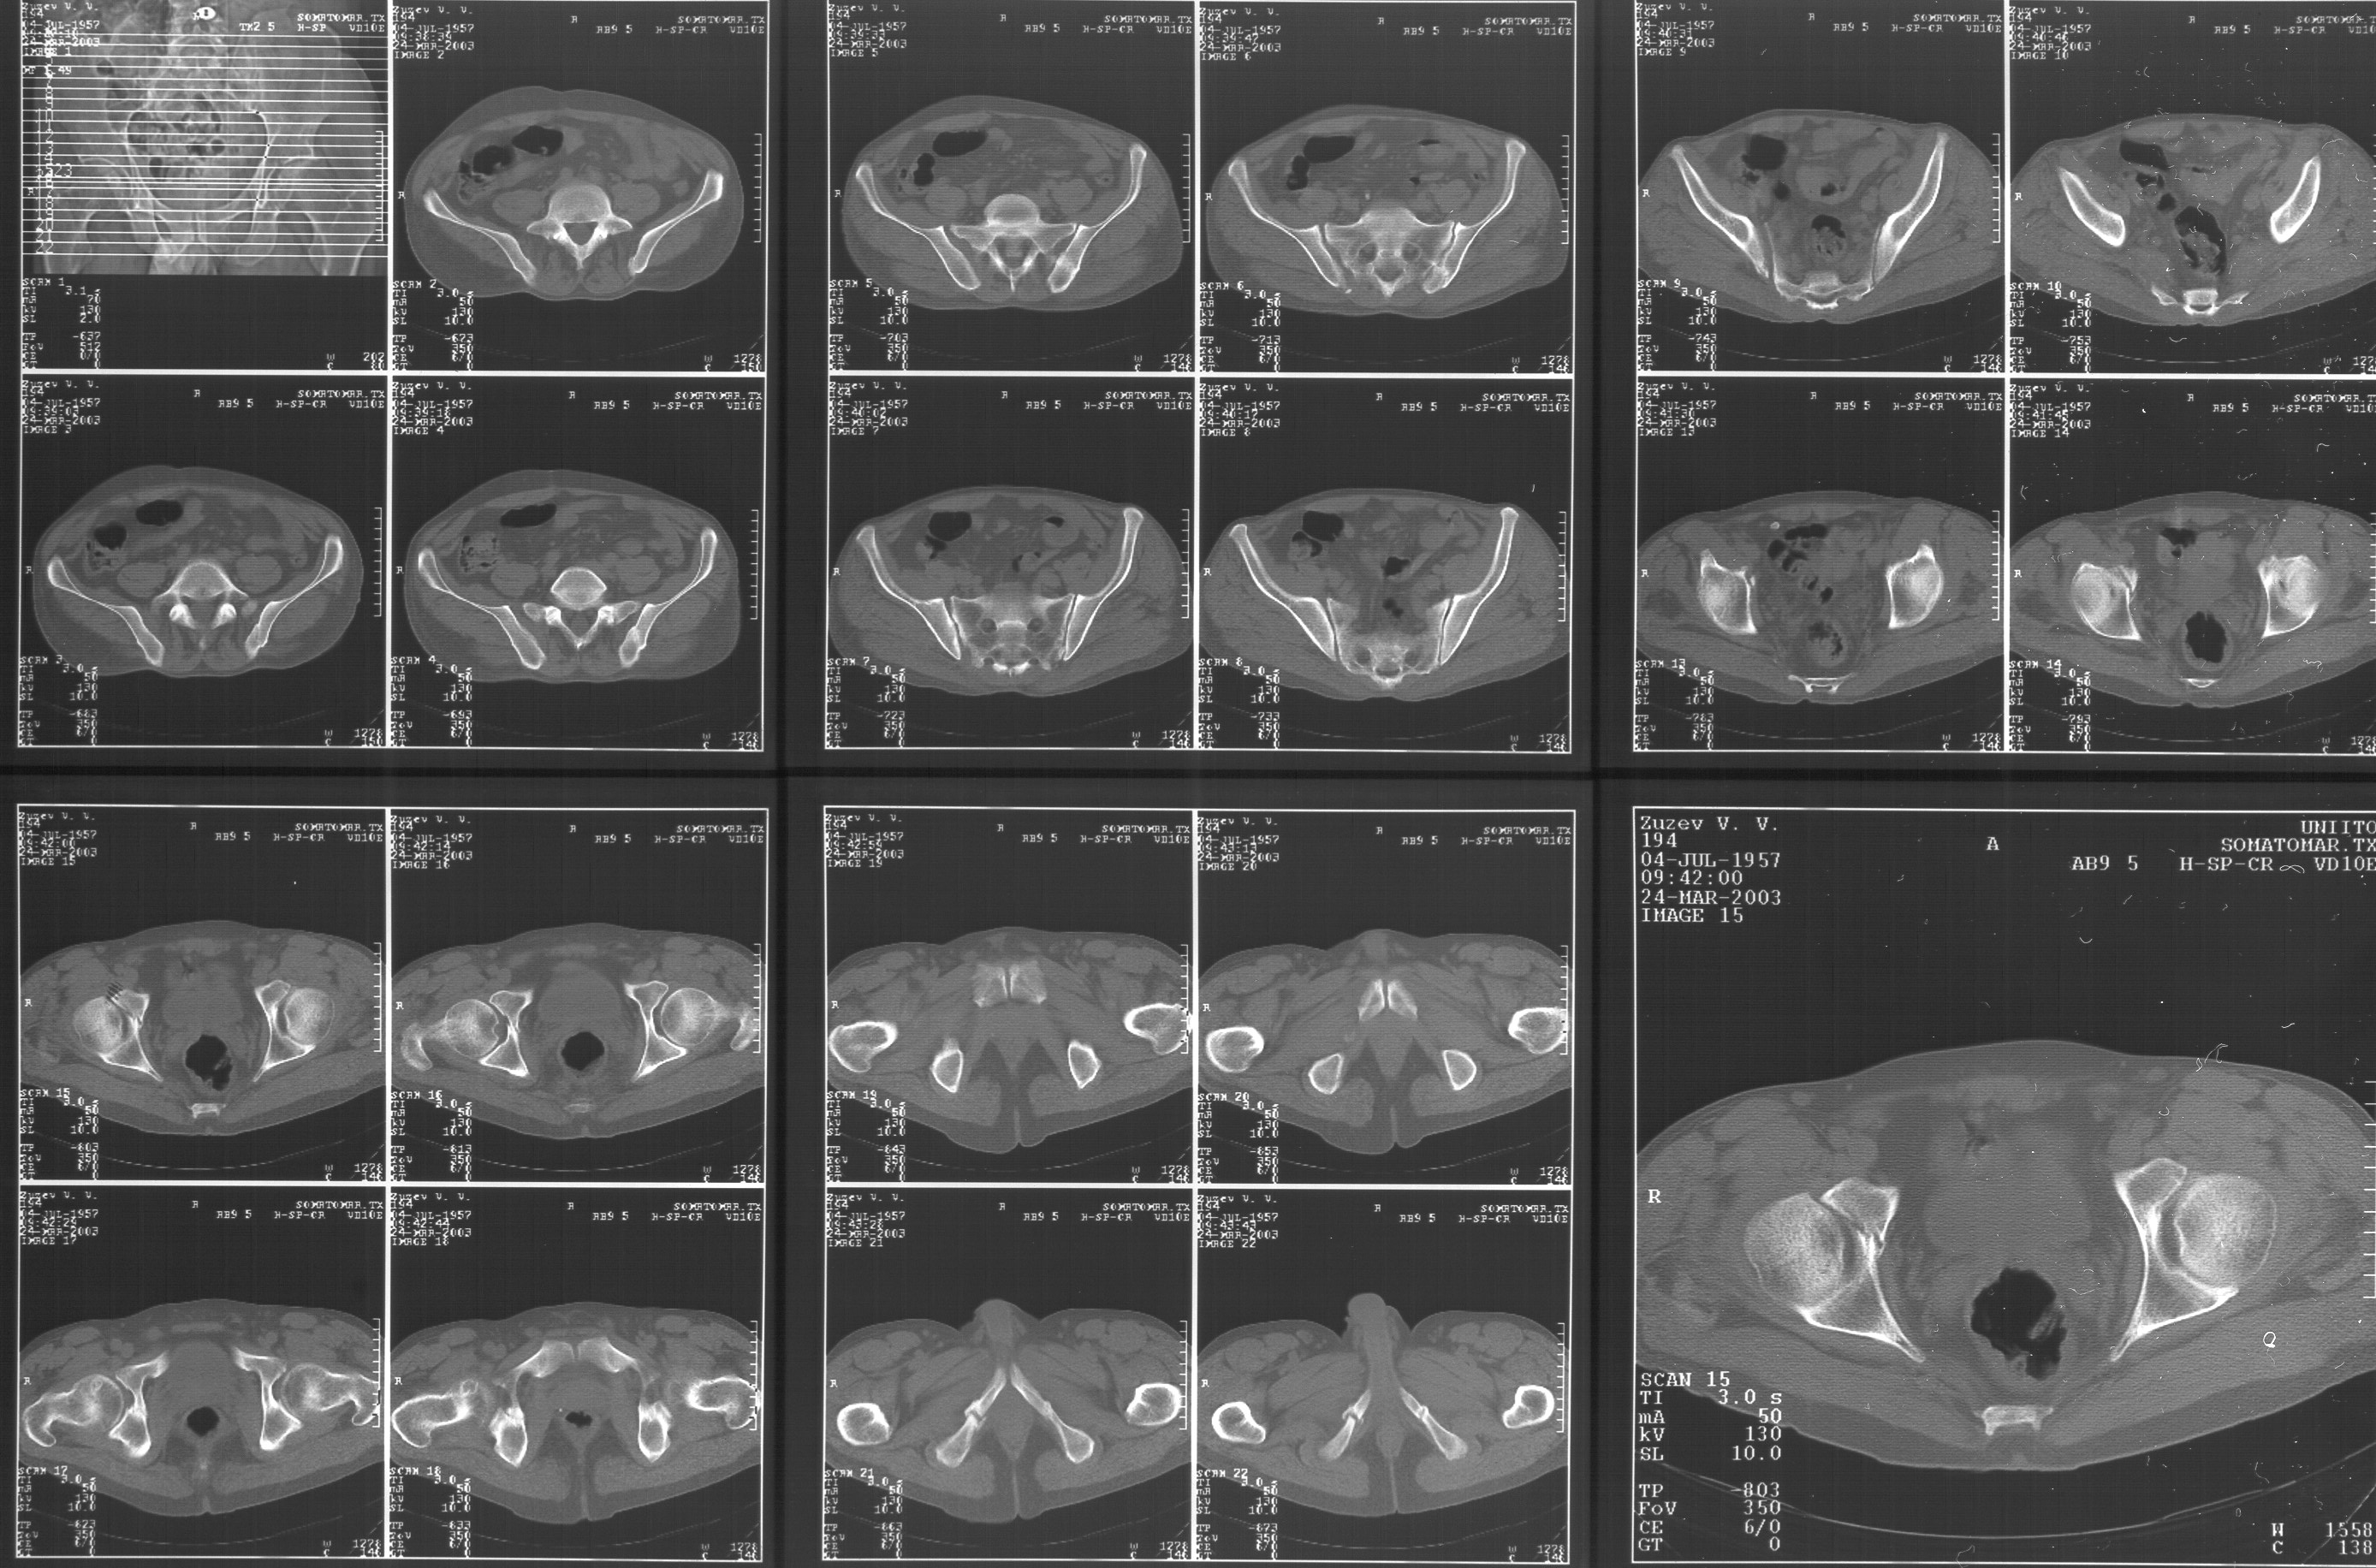

Прилагаю свежую КТ таза.

Буду признателен за комментарии и предложения по тактике.

Картинки см. ниже, левая - с экранным разрешением, вторая - полноразмерная, ~900 кб.

Полноразмрная картинка, около 900 кб